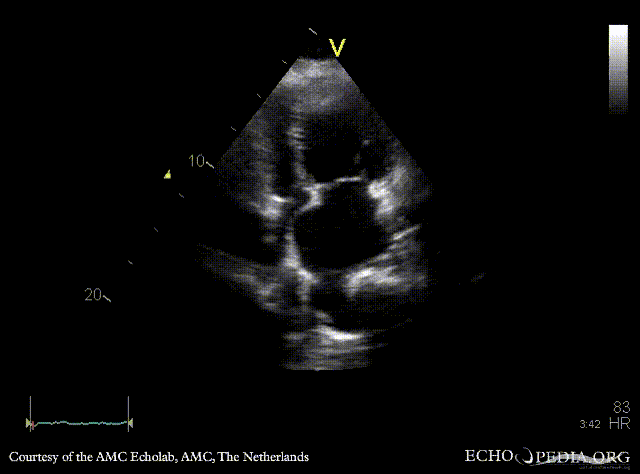

| Courtesy of: AMC Echolab, AMC, The Netherlands | |

| A4CH: dilated pulmonary veins | A4CH with Color Doppler |